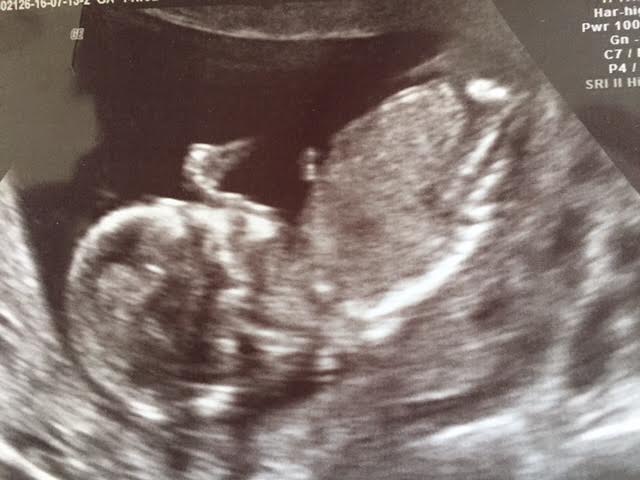

Any gender clues? 15 weeks

I have the most unconvincing set of photos from 15 week u/s!

One photo - Baby is twisted in first pic with its spine facing us partially?

Head on shot looking up at abdomen but nothing between legs?

I thought gender could be diagnosed roughly by 15 weeks as genitals are developed. I'm going crazy wondering why I've got over 10 photos and none show me anything really!

Any help or should I just discard them for gender purposes?! Thank you for any help